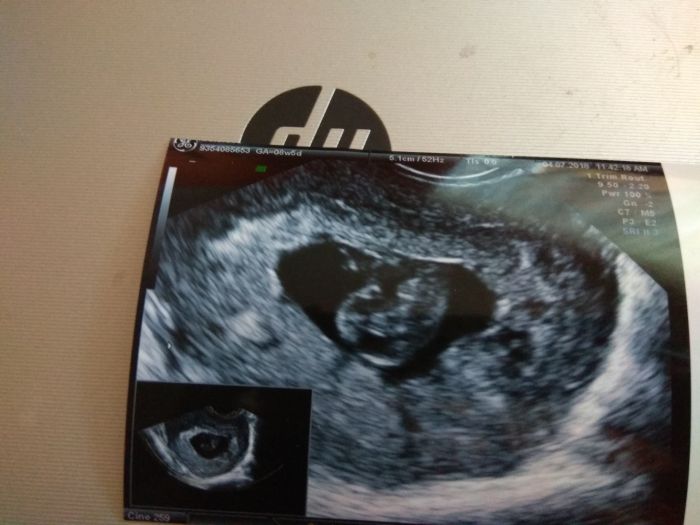

přikládám foto naší fazolky

jinak je to moje první miminko

Ahoj Suzzy,krásná fotka,gratuluju